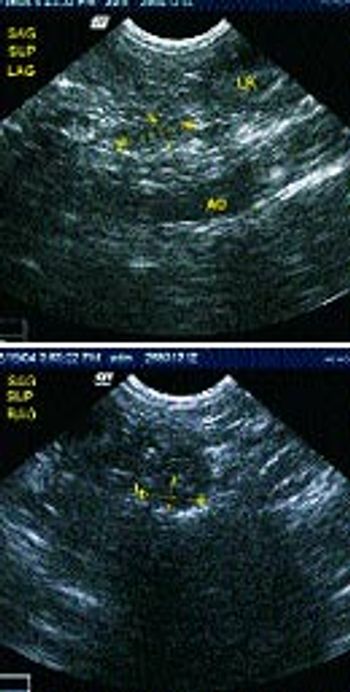

Signalment: Canine, Labrador Retriever, 12 years old, male, 73 pounds.